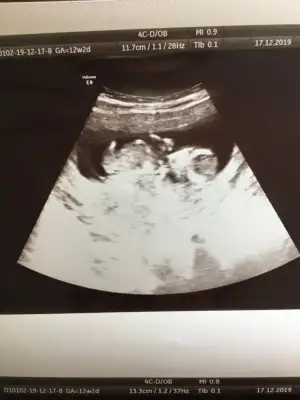

ErkekBunada bakarmisiniz 12 +2 haftalık cok merak ediyorum![]()

Doktor %80 erkek dedi sizce net midir? Cok arkdsm

Bu haftalara guvenme her gittigimde farkli sey soyluyor doktor dedi nuba gorede erkek gibi ama merak ediyorm onceden boyle olup sonra kiz cikan var mi?

12+2 de kıza benziyor dedi. Başka bi tane de şu var ama pek net değil sanki.Başka usg varsa bakayım kaç haftalık usglerde tam detaylı bakamıyoruz dr daha iyi bakar biz usg de ne görürsek dr kaç haftslıkta kız dedi 11 yada 12 hafta olmalı usg nub içşn

Evet bu usgde kız paralel12+2 de kıza benziyor dedi. Başka bi tane de şu var ama pek net değil sanki.